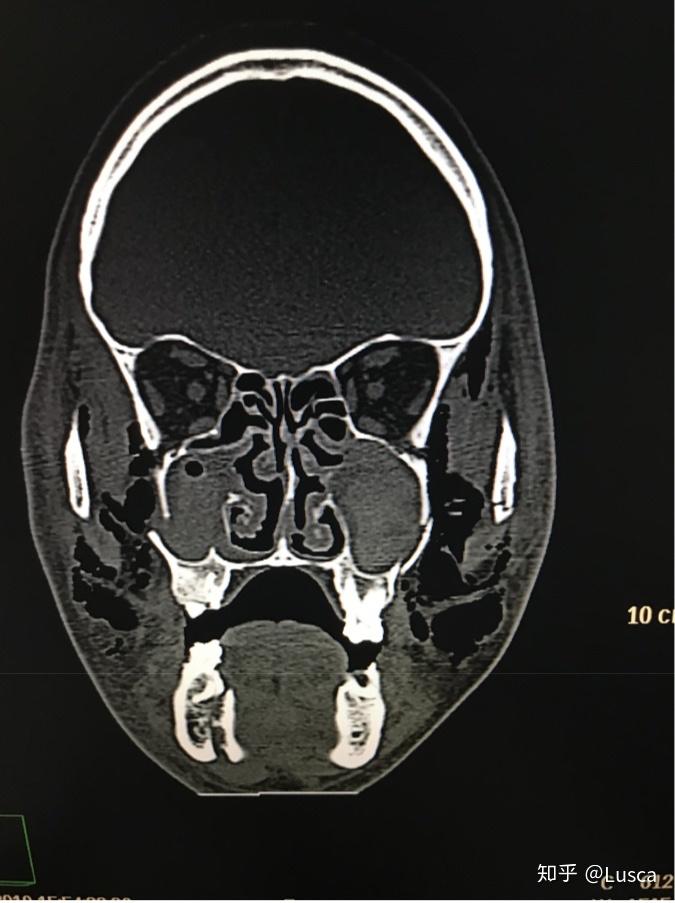

诊断 处理 上颌骨lefort-i骨折,下颌骨颏部骨折.